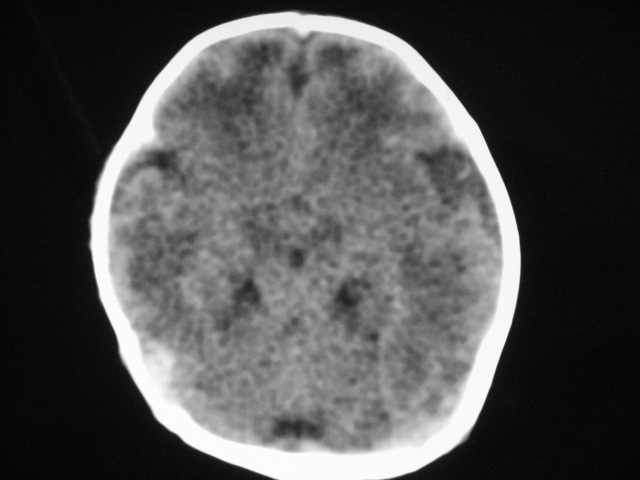

早产儿,1天,饮食呕吐,

双侧额叶见片状低密度灶,皮髓质分界模糊.患儿前囟略饱满,

患儿头颅ct示:皮质薄,髓质密度减低,脑回宽,脑沟浅,脑室系统无殊,中线结构居中,符合:早产儿颅脑ct改变。